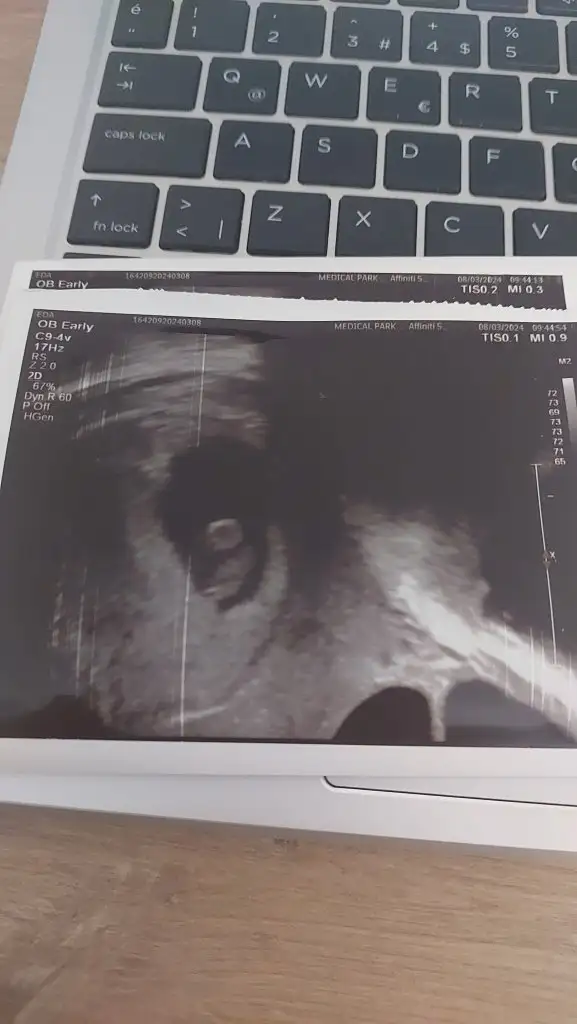

ALttan muayene oldum..cinsiyet tahmini yapan arkadaslar vardi.eglence amacli :) tabiki sagliktan baska onemi yokta.

Bir de kizlar bi ihtimal ikiz olabilir..burda tek bebek yok mu.. yolk sactir dedi. Yakinlastirdi bakti. Haftaya yine gidicem.tup bebekle gebelik olustu.. ama kese tek

Eklentiler

• 1000054032.webp

1000054032.webp

23,7 KB · Görüntüleme: 87

• 1000054033.webp

1000054033.webp

23,3 KB · Görüntüleme: 82

• 1000054034.webp

1000054034.webp

20,4 KB · Görüntüleme: 86